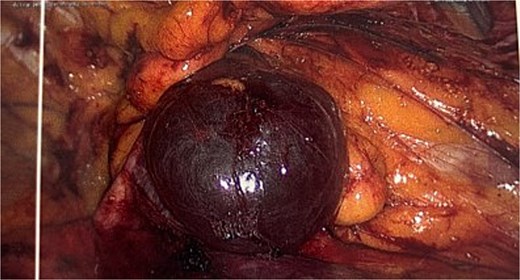

Intraoperative picture following excision of the hydrocele demonstrating the resulting defect.

In up to one third of cases there is an associated inguinal hernia due to the widening of the internal ring [3]. Additionally, to excise the cyst intact may require widening of the neck hence Venkateswaran et al. [7] recommended that the posterior wall should be reinforced with a mesh regardless of the present of a hernia or not due to the future risk of herniation. In this case following excision of the sac this defect is clearly visible (Fig. 3) and would be expected to develop into a hernia if left untreated.